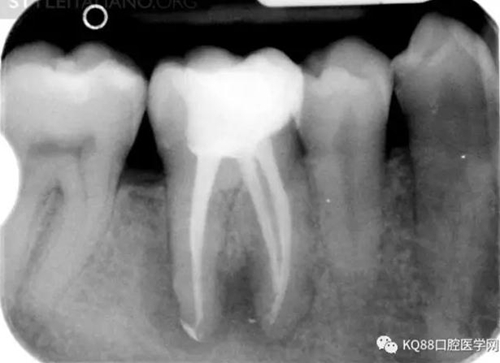

Img. 3 - The frequency of post-endodontic pain is higher in teeth with periapical or periradicular lesions. Infected debris can be forced in the periradicular tissue through a resorpted apex, thus generating acute inflammation. Creating a glide path prior to instrumentation and using a step-down technique can reduce the amount of extruded debris.

Img. 4 - Case 2: This necrotic first mandibular molar was treated in one visit, and the patient complained of post-operative pain. Analgesics and antibiotics were prescribed, and occlusion relieved. Symptoms disappeared after two days, and a radiographic follow-up after two years showed healing of the periradicular lesion.